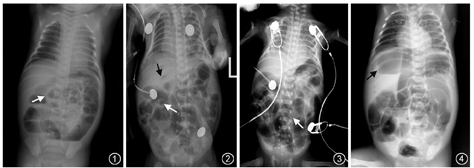

(1)肠管充气减少或肠管充气不均匀,病变肠管形态僵直,位置较固定。(2)肠间隙增厚达3 mm以上。(3)动力性肠梗阻:肠胀气明显,肠管内可有分散的中小气液平面。(4)肠壁积气:发生率为75%~85%,是NEC特征性影像表现。黏膜下积气大多呈囊状或小泡状透亮影,肌层或浆膜下积气显示为沿肠壁的线条状透亮影,或表现为围绕肠管的环状、半环状透亮影。(5)腹腔积液:腹部X线卧位片表现为整个腹部密度增高,两侧胁腹部向外膨隆,肠管漂浮在中央,充气肠管与腹壁间距及肠间隔均增宽、模糊。(6)门静脉积气:NEC较有特征性的征象,显示为肝区自肝门发出的树枝状透亮影,为肠壁内气体经肠系膜静脉和/或淋巴管进入门静脉内的结果,通常在数小时后即消失,但可重新出现,预示病情重、预后差。(7)肠穿孔:X线表现气腹,肠穿孔的发生率为12%~31%,约1/3发生肠穿孔病例可因穿孔较小或被包裹而在X线检查中无法被检出。

本病主要X线征象为肠管充气减少或不均匀,病变肠管形态僵直和肠间隙增厚伴积气,门静脉积气为特征性改变,其他可合并腹腔积液及气腹。